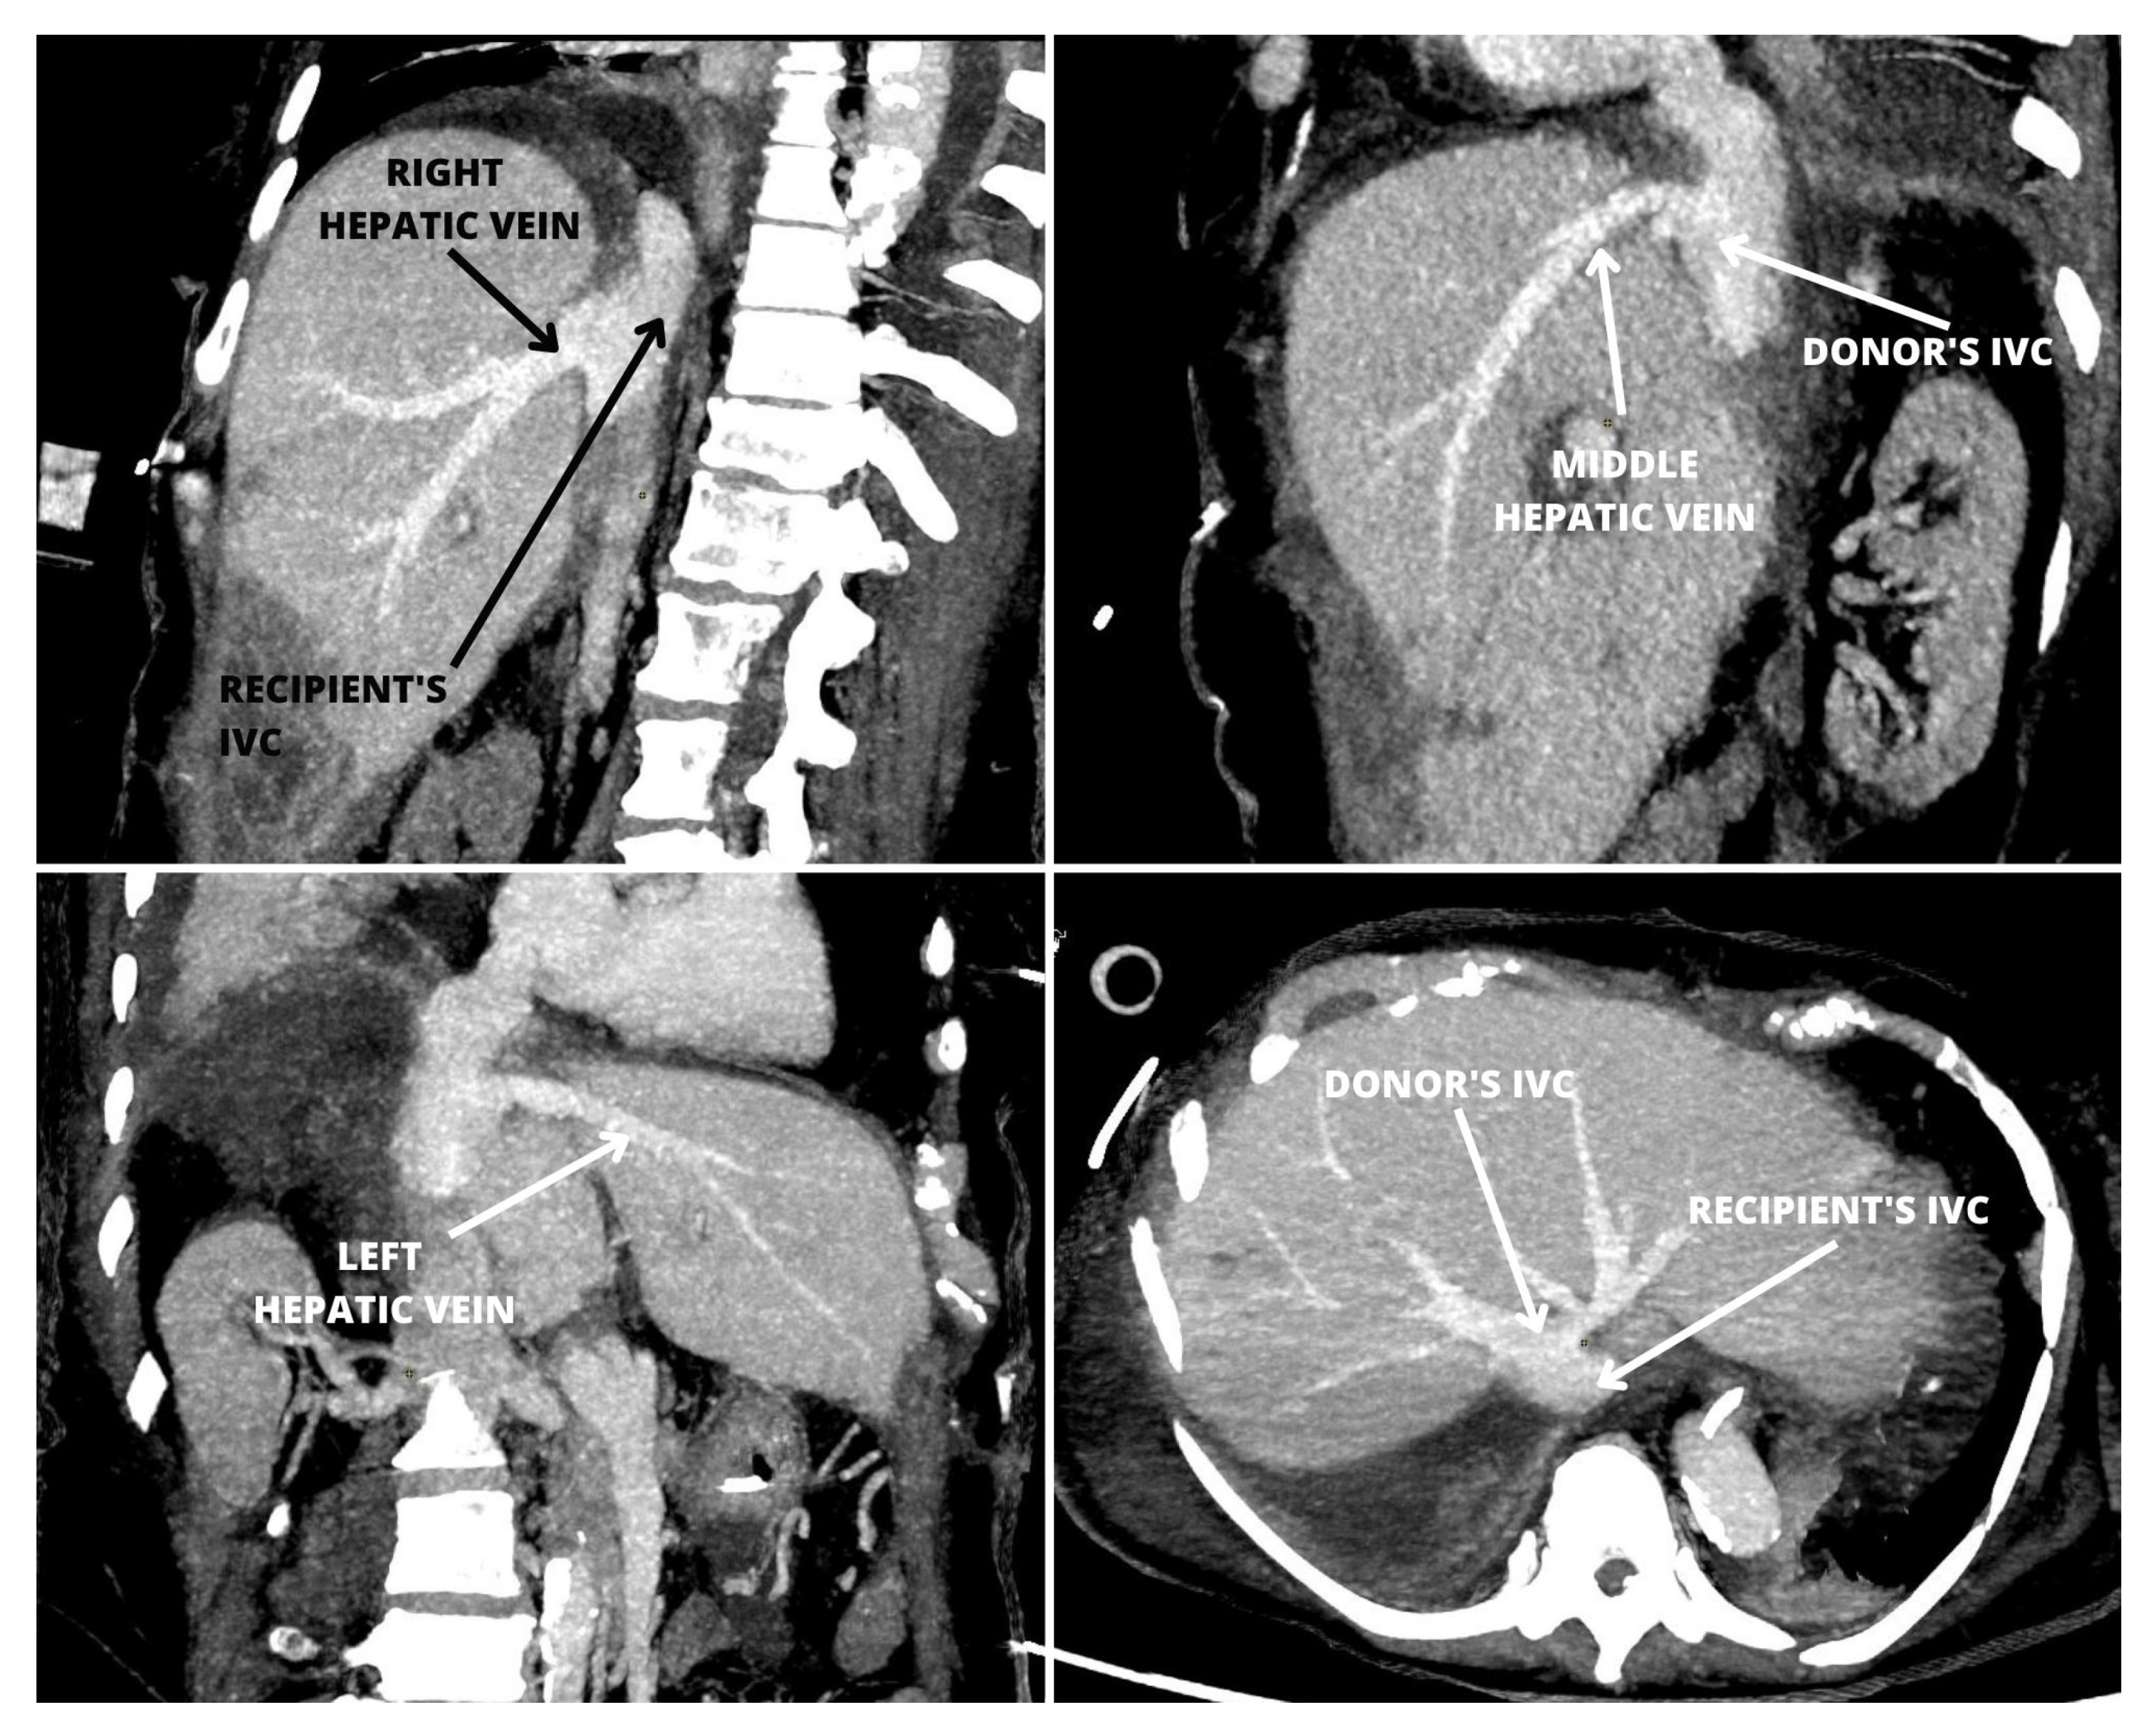

Stapled Anastomosis for Side-to-Side Cavo-Cavostomy in Orthotopic Liver Transplantation

2. Case Report